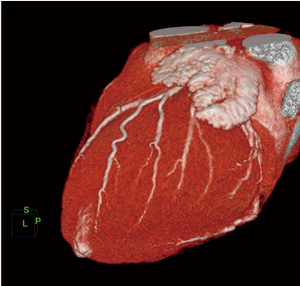

前述した心臓CTの進歩に伴い,1心拍のデータから心臓の拍動を再現できる“4Dイメージ”の作成が可能になった。これは投影画像とは違い,機械弁の開口の状況や僧帽弁,乳頭筋のモーションを三次元的にも自由に回転させてとらえることができるため,心臓の動き・機能の把握に役立つ(図3)。しかし,心臓のデータをクリアに再現させるためには,ばく大なデータ量とレンダリング計算を要することになる。従来の手法では,マシンが持つ資源としての計算量などを考えると,心臓の拍動を再現することはできても,クリアなイメージングで「再現できる」と言えない状況であった。AZEが開発したFORMULAシステムは,前述の負荷分散技術やレンダリング方法の最適化により,データを間引くことも補間することもなく,超高速レンダリングを実現している。撮影された4D心臓データはその場で構築され,無駄な処理を加えない正確な4Dイメージとして,臨床医は確認することができる(図4)。

図3 FORMULAによる高画質心臓拍動画像 特許取得技術PRISMAによって,高画質,高分解能を損なうことなく,4Dイメージを提供できる。

図3 FORMULAによる高画質心臓拍動画像

特許取得技術PRISMAによって,高画質,高分解能を損なうことなく,4Dイメージを提供できる。